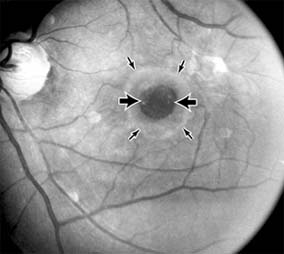

Presumed Ocular Histoplasmosis Syndrome (Figures 10-5, 10-6 and 10-7)

In this disease, serous and hemorrhagic detachments of the macula are associated with multiple peripheral atrophic chorioretinal scars and peripapillary chorioretinal scarring (see Chapter 7). The syndrome usually occurs in healthy patients between the third and sixth decades of life, and the scars are probably caused by an antecedent subclinical systemic infection with Histoplasma capsulatum. The macular detachments are due to subretinal neovascularization, and the visual prognosis depends on the proximity of the neovascular membrane to the center of the fovea. If the membrane extends inside the foveal avascular zone, only 15% of eyes will retain 20/40 vision. A macular scar may change over time, and 10% of patients with normal maculae will develop new atrophic scars in this region. The relative risk of developing macular subretinal neovascularization in the second eye of an affected patient is significant, and these patients should be instructed in the frequent use of the Amsler grid and the importance of prompt examination when changes are detected.

Figure 10-5

Figure 10-5: Presumed ocular histoplasmosis syndrome with active disease (large arrows) and an inactive pigmented macular scar (small arrow). Peripapillary pigmentation (curved arrow) is also present.

Figure 10-6

Figure 10-6: The early fluorescein angiogram shows an inactive hypofluorescent scar (small arrow) and the characteristic lacy hyperfluorescence of subretinal neovascularization (open arrows).

Figure 10-7

Figure 10-7: Late fluorescein leakage from macular subretinal neovascularization in a patient with presumed ocular histoplasmosis syndrome.

Argon laser photocoagulation of a subretinal neovascular membrane outside the foveal avascular zone in symptomatic patients is of value in preventing severe vision loss. The surgical removal of submacular membranes may prove useful in preserving vision.